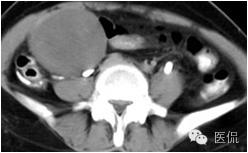

◆CT表现:平扫呈等或稍低密度肿块,低于子宫肌层,可伴少量低密度囊变区,无壁结节

◆增强肿瘤实性成分呈轻-中度不均匀延迟强化,明显弱于子宫肌层;也可无强化